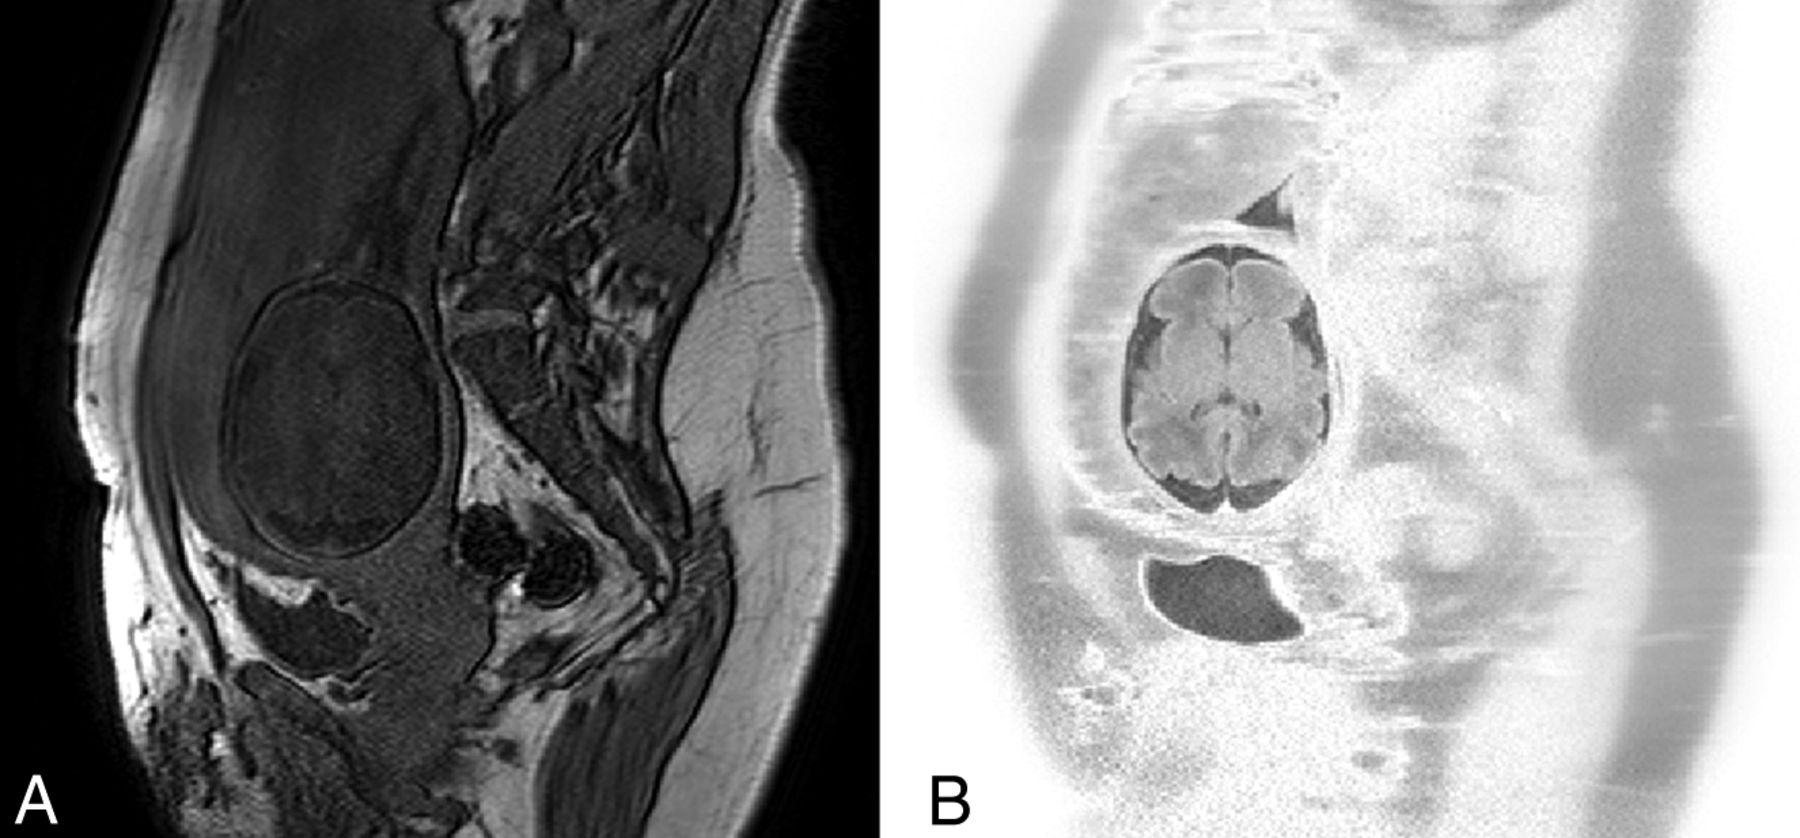

T1-weighted gradient-echo axial brain images at 1.5T (TR, 142 ms; TE, 6 ms; section thickness, 4 mm; scanning time, 16 seconds) of a 28-week-old fetus without motion artifacts after a successful breath-hold (A) and with motion artifacts after an incomplete breath-hold (B). Breathing artifacts appear in the form of high-signal ghosts in the operator-selected phase-encoding direction and severely degrade image quality.

Motion in the fetal and neonatal MR imaging context may be predictable (eg, maternal respiratory motion, Fig 3), but in most cases, it is random and unpredictable (ie, fetal movements in utero or neonatal head movements ex utero). In general, motion may be continuous throughout the MR imaging acquisition (eg, an unsettled neonate), periodic (eg, respiratory motion), or intermittent (eg, provoked by MR imaging scanner acoustic noise). In neonatal and fetal brain imaging, motion can be assumed to be rigid body motion, with minimal or no deformation and with all dimensions of the imaging target being preserved.13 Motion can be restricted in a 2D field, involving rotation and translation within an acquired imaging section or it may be 3D, including also through-plane motion, with rotations and translations potentially spanning different sections; through-plane motion is one of the most difficult to compensate for. Most important, both fetal and neonatal motion (with amplitudes in the range of a few centimeters14) can be relatively greater than that of adults (with amplitudes in the range of a few millimeters) and also of a scale greater than the actual dimensions of the anatomy of interest; therefore, its effects on image quality are often detrimental.